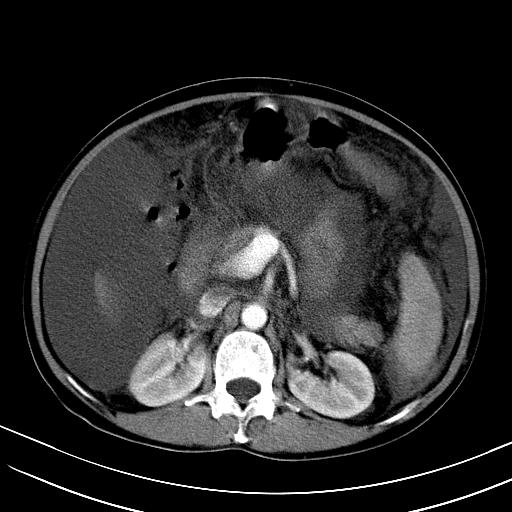

标题: CT23697:肝癌并肝动静脉漏? [打印本页]

标题: CT23697:肝癌并肝动静脉漏?

肝动静脉漏,动脉期肝动脉及门静脉内均可见造影剂……

1)肝右叶肝癌并肝动静脉漏。2)肝硬化,腹水。3)胆囊炎。

肝右叶肝癌并动静脉漏,肝硬化,腹水。

1)肝右叶肝癌并肝动静脉漏 门v右支瘤栓伴海绵样变。2)肝硬化,脾大 腹水。3)胆囊炎。门v高压.

右叶肝癌并肝动静脉漏(动脉期肝动脉及门静脉内均可见造影剂),肝硬化,腹水。(胆囊壁水肿)

1)肝右叶肝癌,考虑并发肝动静脉漏。扫描时间好像慢了。2)肝硬化,门脉高压、脾大、腹水。